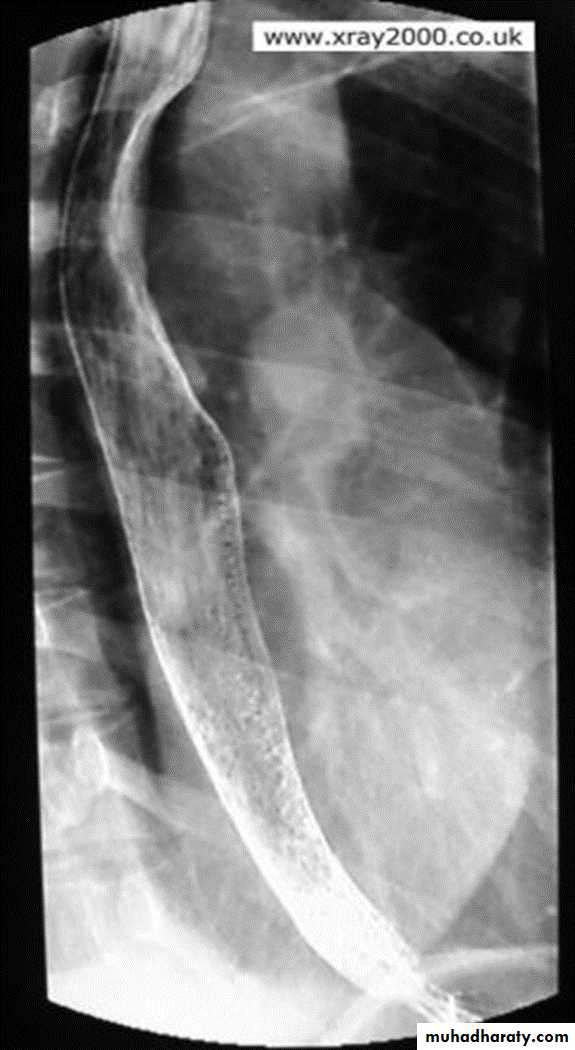

Malignant stricture

CA esophagus is the cause for the malignant stricture

The most common types of esophageal carcinoma are squamous cell carcinoma and adenocarcinoma .

esophagography is unique among esophageal studies for assessing both morphology and motility. Barium esophagography remains the study of choice for characterization of esophageal strictures. Esophageal carcinoma may demonstrate a variety of appearances on barium esophagrams.

Annular Carcinoma

Narrowing :

1-Constant.

2-Irrigular .

3-Variable length.

4- Shouldering sign.

5-Fistula (double tract).

6-Soft tissue shadow of the mass